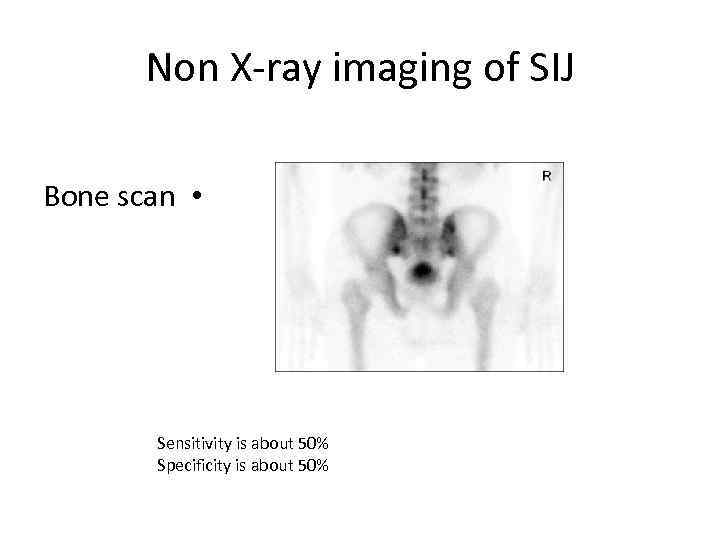

Non X-ray imaging of SIJ Bone scan • Sensitivity is about 50% Specificity is about 50%